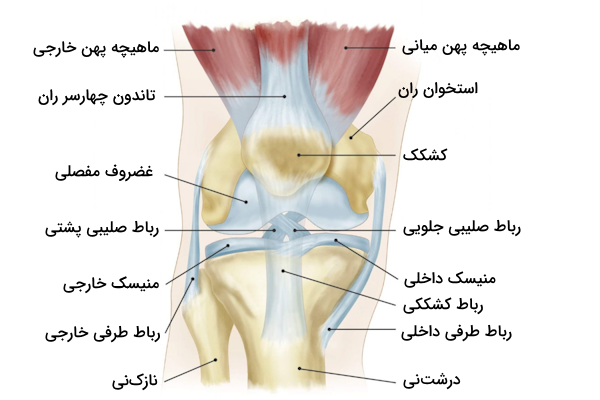

استخوانهای زانو

با بررسی آناتومی زانو متوجه میشویم که مفصل زانو از سه استخوان ساخته شده است.

- استخوان ران یا فمور

- استخوان درشت نی یا تیبیا

- کشکک یا پاتلا

در انتهای استخوان ران دو سطح مفصلی گرد وجود دارند که به آن «کوندیل» (Condyle) میگوییم. کوندیلهای استخوان ران در مقابل دو سطح مفصلی روی استخوان درشتنی قرار دارند که به نسبت صاف به نظر میرسد اما در حقیقت اندکی مقعر است. رباطهای صلیبی که یکی از انواع رباطهای مفصل زانو هستند از فاصله بین دو کوندیل میگذرند و به دو برجستگی کوچک متصل میشوند که بین کوندیلهای استخوان ران و استخوان درشت نی قرار دارند.

کشکک زانو در بخش جلویی استخوان ران قرار دارد و به کمک تاندون زانو یا «تاندون کشککی» (Patellar Tendon) که با عنوان رباط کشکی نیز شناخته میشود، به درشتنی متصل میشود. سطح داخلی کشکک زانو گُوِهای شکل است و با غضروف مفصلی پوشیده شده است؛ این سطح در حین خم یا صاف شدن زانو در امتداد شیاری که روی استخوان ران وجود دارد، میلغزد. استخوان کشکک زانو مانع از لغزش جانبی تاندون میشود، همچنین میتواند اثر استخوان ران به عنوان یک اهرم را افزایش دهد که نتیجه آن تقویت انتقال نیرو است.

آناتومی رباطهای زانو

با بررسی آناتومی زانو متوجه میشویم که رباطهای مفصل زانو به دو دسته تقسیم میشوند که آنها را با عنوانهای زیر میشناسیم.

این رباطها ضمن متصل کردن فمور یا استخوان ران را به تیبیا یا درشتنی ، آن ها را در جای خود نگه میدارند و از جابهجا شدن موقعیت مکانی این استخوانها جلوگیری میکنند، بنابراین میتوان گفت حفظ ثبات مفصل زانو برعهده رباطها است. رباطهای خارجکپسولی در بخش خارجی کپسول مفصل دیده میشوند و شامل رباطهای زیر هستند.

- «رباط کشککی» (Patellar Ligament)

- «رباط طرفی خارجی» (Lateral collateral Ligament | LCL)

- «رباط طرفی داخلی» (Medial collateral Ligaments | MCL)

رباط کشککی

رباط کشککی نواری فیبری است که از ادامه بخش انتهایی تاندون عضله چهارسر ران ایجاد میشود. این رباط ضخیم و مقاوم در بخش سطحی یا جلویی بورس زیرکشککی دیده میشود. به طور دقیقتر میتوان گفت که محدوده مربوط به رباط کشککی از نوک کشکک آغاز شده و تا «برجستگی استخوان درشت نی» (Tibial Tuberosity) ادامه مییابد. رباط کشککی نقش مهمی در تثبیت کشکک و جلوگیری از جابجایی آن ایفا میکند.

منیسکهای زانو

منیسکهای زانو صفحاتی هلالی شکل از جنس «فیبروکارتلاژین» (Fibrocartilaginous) هستند که در سطوح مفصلی فمور و تیبیا (استخوان ران و درشتنی) وجود دارند. منیسکها دو نقش بسیار مهم برعهده دارند.

در زانو دو منیسک داخلی و خارجی وجود دارد که هر دو آنها به انتهای ناحیه بین کوندیلی استخوان درشت نی متصل هستند. منیسک داخلی اتصالات دیگری نیز دارد که به شرح زیر هستند.

منیسک داخلی زانو

منیسک خارجی زانو

ماهیچههای اطراف زانو